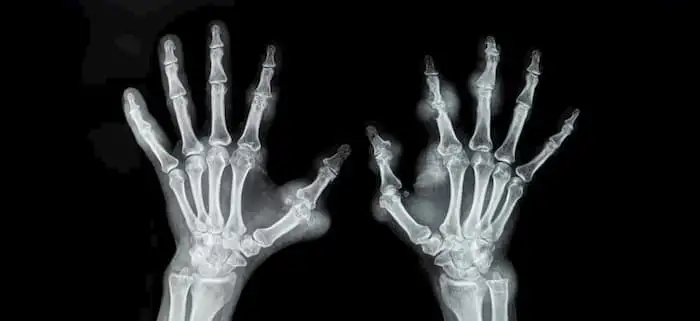

Synthetic and biological DMARDs are beneficial for the management of individuals suffering from rheumatoid arthritis.

The updated EULAR recommendations published in "The Annals of the Rheumatic Diseases" offered consensus on rheumatoid arthritis management encompassing effectiveness, cost, and safety. This study aimed to offer an update on the management guidelines for rheumatoid arthritis that takes into account the most recent scientific advancements. A global task group was established, and 3 systematic literature reviews on the effectiveness and safety of disease-modifying antirheumatic drugs (DMARDs) and glucocorticoids were requested. With reference to the most recent update from 2019, the newest evidence was discussed. Each guiding concept and recommendation was put to a vote according to a predetermined process.